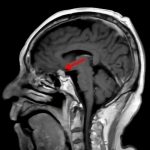

断層撮影